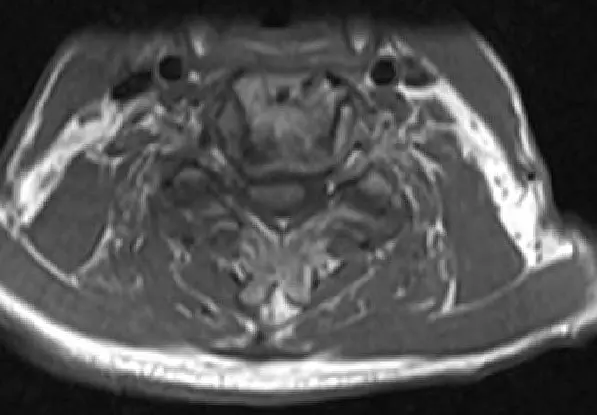

MRI T2 image Axial cut showing severe spinal cord stenosis and compression at C3-4

MRI T2 image Axial cut showing severe spinal cord stenosis and compression at C3-4